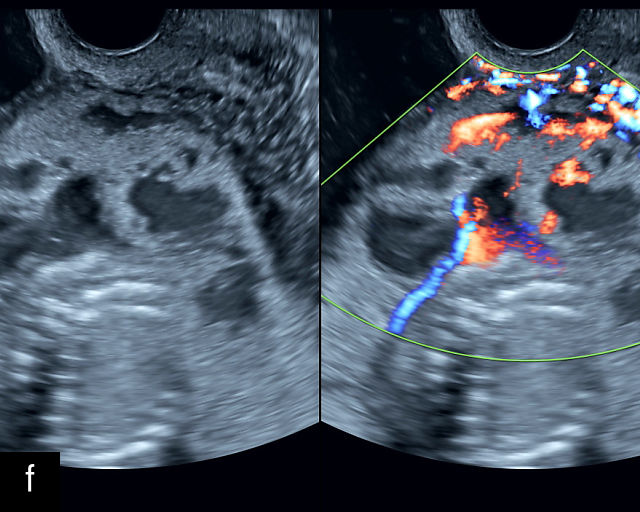

Placenta previa and low-lying placenta. (a) Transabdominal grayscale ultrasound image suspicious for placenta previa. The placenta (PL) appears to overlie the internal cervical os (CX). Note the time stamp: 2:19:37. (b) Transvaginal ultrasound of the same patient taken approximately 50 minutes later. Note the time stamp: 3:10:25. The internal os and the lower placental edge are both clearly seen, and the placenta does not overlie the internal os. Because the lower placental edge is 1.93 cm from the internal os, it will likely resolve by the third trimester. (c) Transabdominal grayscale ultrasound of placenta previa. The placenta (p) covers the cervix, but the cervix, especially the internal os, cannot be visualized due to shadowing. (d) Transabdominal grayscale ultrasound of placenta previa. The placenta (p) covers the cervix (c) but shadowing obscures adequate visualization. The internal os is indicated by the arrow. (e) False-positive image of placenta previa on transabdominal grayscale ultrasound. The bladder (b) is full, pushing the anterior and posterior walls of the lower uterine segment (ls) together making it appear that the placenta (p) overlies the internal os of the cervix. In reality, the line depicted by the arrowheads is where the anterior and posterior walls of the lower segment are in proximity to each other. The cervix is much lower and is obscured by shadowing (c). (f) Transabdominal grayscale ultrasound image of placenta previa. The placenta (p) covers the cervix (c), but the cervix, especially the internal os, cannot be visualized due to shadowing. b, bladder. (g) Transvaginal grayscale ultrasound image of placenta previa. The placenta (p) completely covers the internal os (arrow) of the cervix (c). The internal os can be seen clearly. h, fetal head. (h) Transvaginal grayscale ultrasound image of posterior low-lying placenta (p). The lower placental edge is clearly seen and is 1.56 cm from the internal os (arrow) of the cervix (c). The placental edge and the internal os are clearly seen. h, fetal head. (i) Transvaginal grayscale ultrasound image of a posterior placenta previa (p). The internal cervical os is clearly seen (arrow). c, cervix. (j) Transvaginal grayscale ultrasound image of an anterior placenta previa (p). The internal cervical os is clearly seen (arrow). c, cervix; h, fetal head. (k) Transvaginal grayscale ultrasound image of a posterior placenta that was thought to be low-lying on transabdominal sonography but could not be adequately assessed. This examination clearly shows the lower edge of the placenta (p) to be 2.18 cm from the internal os (arrow) of the cervix, firmly establishing that the placenta is not low-lying and allowing the patient to undergo labor safely and deliver vaginally. c, cervix. (l) Transvaginal grayscale ultrasound image of placenta previa. The placenta (p) completely covers the internal os (arrow) of the cervix (c). The internal os can be seen clearly.

Most cases of placenta previa will be suspected prenatally by transabdominal ultrasound.49 However, this approach has several limitations and may be inaccurate.72,73,74 because the relationship between the placenta and the internal cervical os may be difficult to assess by transabdominal ultrasound.72,73,74 The bladder may be full, pushing the anterior and posterior walls of the lower uterine segment together, falsely creating the impression of a placenta previa (Figure 5e).61 There may be considerable shadowing, including by the fetal presenting part, which may limit the accuracy of transabdominal ultrasound (Figure 5d,f).75 Posterior placentas may be more difficult to assess.

Transvaginal ultrasound overcomes these limitations (Figure 5g–l).72,73,74,76 The probe is inserted into the vagina and therefore is closer to the region of interest.51,61 In addition, transvaginal transducers have higher frequencies and superior resolution compared to transabdominal transducers. Transvaginal ultrasound is safe and is not associated with increased bleeding.72,73,74,75,76 As such, transvaginal ultrasound should be the imaging modality of choice whenever there is suspicion of placenta previa.49,67,77